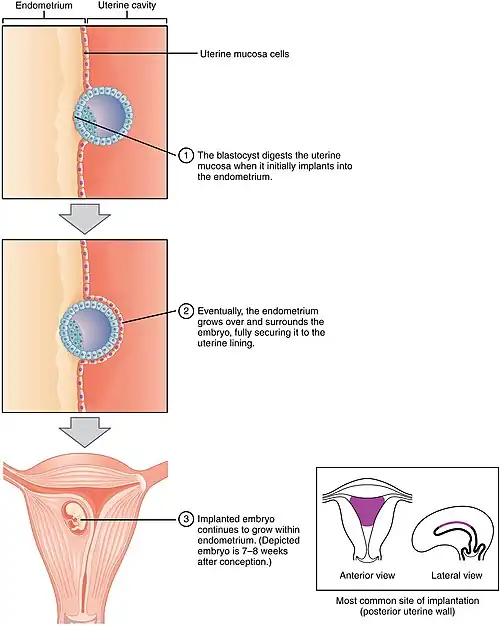

De ovulatie (eisprong) vindt gemiddeld twee weken na de eerste dag van een menstruatie plaats, als zwangerschap volgt dus bij een PML van twee weken. Binnen een etmaal daarna vindt dan de bevruchting (conceptie) plaats, waarbij een zaadcel een eicel bevrucht, waardoor er een zygote (bevruchte eicel) wordt gevormd. De zaadcel is over het algemeen afkomstig van een ejaculatie (zaadlozing) in de vagina bij vaginale geslachtsgemeenschap, niet meer dan drie etmalen voor de bevruchting. Circa zes dagen na de bevruchting volgt de innesteling, de nidatie van het embryo (de morula) in het baarmoederslijmvlies van de baarmoeder. Na een bevruchting blijven daaropvolgende menstruaties uit. Een zwangerschapstest is over het algemeen zinvol vanaf de dag dat de eerstvolgende menstruatie wordt verwacht: de test is, in het geval van zwangerschap, in het algemeen positief vanaf die dag of 1 à 2 dagen later. Eerder is de kans op een fout-negatieve uitslag groot.

Voor de innesteling deelt de zygote zich in kleinere cellen, een klompje totipotente (nog ongedifferentieerde) cellen dat zich excentrisch in de blastocyste bevindt. Circa zes dagen na de bevruchting, dus bij een PML van 3 weken, zijn er 16 tot 32 cellen en volgt de innesteling (nidatie) van het embryo (de morula) in het baarmoederslijmvlies (endometrium).

Innestelingsbloeding

Een aantal zwangere vrouwen krijgt nog een bloeding op het moment dat hun volgende menstruatie had moeten komen. Deze bloeding wordt veroorzaakt door het bevruchte embryo dat zich innestelt in het baarmoederslijmvlies. Zo'n implantatiebloeding gaat doorgaans met minder bloedverlies en minder buikkrampen gepaard. Bloedverlies in het verdere verloop van de zwangerschap kan heel onschuldig zijn, maar men doet er toch goed aan in een dergelijk geval een arts te raadplegen. Het kan immers ook wijzen op een dreigende miskraam, zeker als de bloeding hevig en pijnlijk is.